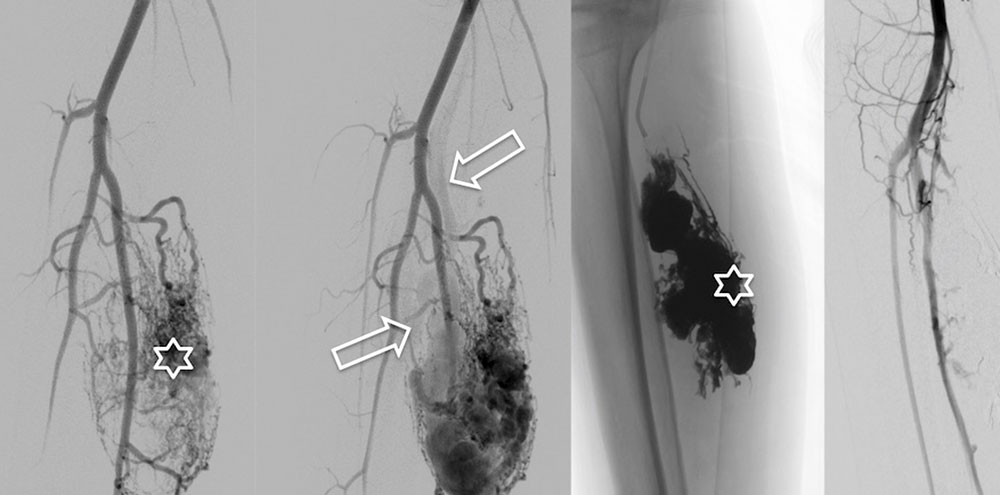

Die perkutane Embolisation ist nach wie vor die Therapie der ersten Wahl. Bei sehr großen arteriovenösen Malformationen müssen mehrere Behandlungssitzungen geplant werden. Über einen transarteriellen Zugang, eine Angiographie werden der Nidus sowie die frühen Drainagevenen der arteriovenösen Malformation mit permanenten Flüssigembolisaten verschlossen. Als Flüssigembolisate werden Ethylen-Vinyl-Alkohol-Kopolymere, N-butyl cyanoacrylat (nBCA) sowie in seltenen Fällen auch hochprozentiges Ethanol appliziert.

Da die arterielle Versorgung des umliegenden, nicht betroffenen Gewebes geschont werden muss und eine Embolisatverschleppung in gesunde Gefäße absolut zu vermeiden ist, erfordert die Applikation des Embolisats eine große Erfahrung des Anwenders. Lässt es die Angioarchitektur der arteriovenösen Malformation zu, dass nur wenige Drainagevenen vorliegen, so ist eine Embolisation über einen retrograden transvenösen Zugang oder einen direkten perkutanen Zugang perkutane Katheterembolisation eine sehr erfolgversprechende Alternative.